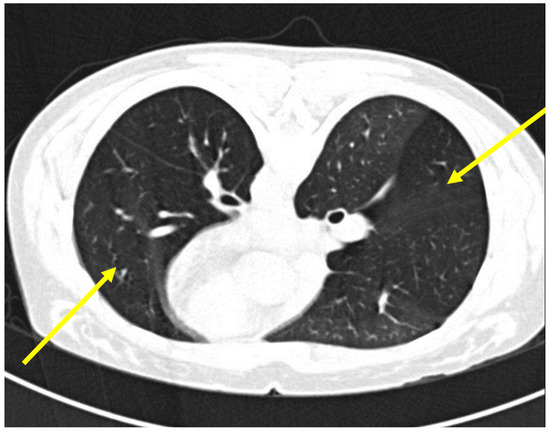

Background: Lymphomatoid granulomatosis (LYG) is a rare and atypical EBV-induced B-cell lymphoproliferative disorder. Clinical manifestations are mainly respiratory, with nodular infiltrates, varying in number and size, being responsible for respiratory distress. Cutaneous, hepatic, or neurological involvement is also possible. Although pathogenesis is not

Background: Lymphomatoid granulomatosis (LYG) is a rare and atypical EBV-induced B-cell lymphoproliferative disorder. Clinical manifestations are mainly respiratory, with nodular infiltrates, varying in number and size, being responsible for respiratory distress. Cutaneous, hepatic, or neurological involvement is also possible. Although pathogenesis is not clearly elucidated, quantitative or qualitative cellular immunodepression is thought to be a main factor. Here, we report a case of concomitant LYG and pulmonary tuberculosis. Case presentation: An 80-year-old female patient presented to the emergency unit for steadily increasing dyspnea, with workup revealing bilateral pulmonary nodules and mediastinal lymph node enlargement on chest imaging. Empiric antibiotic therapy was initially started with amoxicillin-clavulanate, which was later combined with azithromycin following respiratory deterioration. A CT-guided lung biopsy showed grade 2 LYG. Treatment with corticosteroids and weekly rituximab was initiated, leading to rapid improvement of respiratory symptoms. After the second dose of rituximab, sputum cultures that were initially collected were found to be positive for Mycobacterium tuberculosis. Rituximab was suspended, and antituberculous treatment was initiated. Rituximab was restarted once tuberculosis was controlled. Follow-up imaging later showed adequate control of both tuberculosis and LYG, with at least a partial remission of the latter. Conclusions: Our case highlights the importance of a complete diagnostic workup when a diagnosis of LYG is made, to avoid missing a concomitant pulmonary disease, such as tuberculosis, even when definite pathologic and clinical features of the former are present.

Figure 1